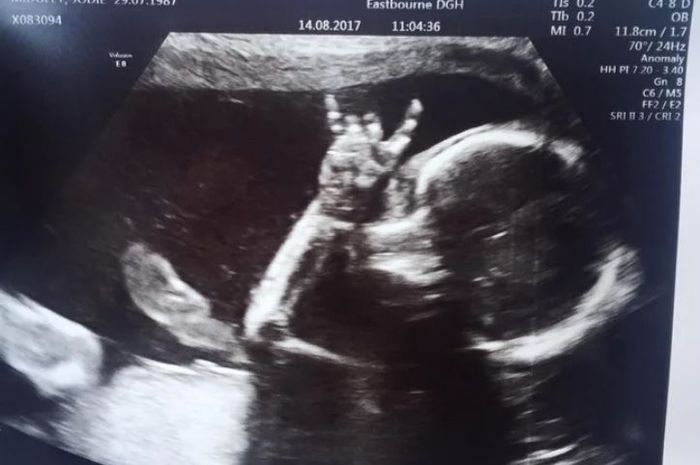

Kenali Cara Membaca Hasil USG Untuk Tahu Kondisi Bayi - Ibupedia Risiko Bayi Lahir dengan Berat Badan Rendah Bisa Dideteksi dengan USG Moms, Begini Caranya Membaca Hasil USG : Okezone Lifestyle 5 Langkah Membaca Hasil USG yang Bisa Bunda Pelajari Terekam USG, Janin Bayi Kembar Ini Saling Adu Jotos dalam Kandungan Ibunya - Semua Halaman - Grid Hot Unik! Tangan Bayi Ini Bentuk Simbol Rock N’ Roll Saat Di-USG Kesalahan Memprediksi Jenis Kelamin Saat Awal Kehamilan - kumparan.com Penjelasan di Balik Bayi Bisa Tersenyum di dalam Kandungan Viral, Rekaman USG Bayi Kembar Bertengkar dalam Rahim - Citizen6 Liputan6.com Tak Usah USG, Ini Cara Sederhana Ketahui Jenis Kelamin Bayi - Tribun Sumsel Orangtua Kaget Bukan Main saat Hasil USG Menunjukkan Bayi Melakukan Simbol Metal - Semua Halaman - Suar Ini Dia Cara Membaca Hasil USG dengan mudah - Mamapapa.id % USG Aman bagi Janin, Asalkan… Waduh, Hasil USG Tidak Bisa Dipercaya 100 Persen - Warta Kota Hiii, Hasil USG 4D Ini Tunjukkan Wajah ‘Bayi’ yang Menyeramkan Penampakan Wajah Misterius Muncul dalam Hasil USG Bayi Ini - Global Liputan6.com Hasil USG Bayi Yang Seram Ini Bisa Kasih Kamu Mimpi Buruk - ANTVKLIK Selain USG, 2 Cara Ini Terbukti Secara Ilmiah Tebak Kelamin Bayi - Berita Riau Terkini TULISAN 11. DETEKSI KELAINAN JANIN DENGAN USG – Dr. Cucuk Santoso Sp.OG Benarkah USG Membahayakan Kondisi Janin di Dalam Kandungan? | Indozone.id Cara Membaca Hasil USG yang Benar, Wajib Tahu! Gambaran Hasil Usg Kehamilan 5 Minggu Yang Perlu Diperhatikan - Hamil.co.id Viral Foto Hasil USG Perlihatkan Janin Kembar Sedang Berkelahi - Citizen6 Liputan6.com Pamer Foto USG, Bayi Nina Zatulini Sudah Mancung di Kandungan Bikin Ngeri ! ini Gambar-Gambar Hasil Ultrasonografi (USG) Terseram - Semua Halaman - Nakita Ini Dia Perbedaan USG 2D, 3D, 4D, dan 5D yang Ibu Hamil Perlu Tahu | BukaReview Manfaat USG untuk Ibu Hamil dan Janin - Ibupedia Pentingkah USG 4 Dimensi? - Mommies Daily Lihat Foto-foto Hasil USG Ini Bikin Merinding, Wajah Bayinya Menyeramkan! - Tribun Lampung Di Indonesia Juga Bisa, Sekarang Ibu Tunanetra Bisa Melihat Bayi dalam Kandungannya - Kompasiana.com Prosedur USG NT Bisa Deteksi Kelainan Janin Lebih Awal | Parenting.Dream.co.id Dokter Jelaskan Hasil USG yang Tampilkan Sosok Bayi Iblis | Republika Online USG BAYI PEREMPUAN DALAM KANDUNGAN USIA 6 BULAN - YouTube Ini Rata-Rata Berat Janin 5 Bulan - Alodokter Viral Video USG Bayi Kembar Berantem Dalam Perut Ini Bikin Gemas - Hot Liputan6.com Viral Foto USG Bayi Disebut Mirip Setan, Sang Ibu Tetap Mencintainya Berapa Kali USG Saat Hamil Harus Dilakukan? Bumil Wajib Tahu, Inilah Penyebab Bayi Sungsang dan Cara Mengatasinya Perkembangan Janin Umur 15W dalam Kandungan - Armita Consultant Gambaran USG janin perempuan usia kehamilan 29 minggu 3 hari - YouTube USG 4D Deteksi Janin Dalam Rahim - Rumah Sakit Permata Cara Membaca Hasil Foto USG Kehamilan - Cara Mengetahui Jenis Kelamin Janin Hasil USG Kehamilan 24 Minggu : “Istriku Hamil Mobil Sport!” | theAsianparent Indonesia Apakah USG Pengaruhi Perkembangan Bayi dalam Kandungan? – Islampos Ibu Panik Karena Corona, Hasil USG Janin Acungkan Dua Jari Ini Bikin Heran | merdeka.com USG foto hasil usg bayi perempuan di bali | wordsof.sandybali.com Story of My Journey: USG Kehamilan 19 Minggu 10 Foto USG bayi ini bikin merinding, mirip karakter film horor Tak Pernah Tes USG, Bayi Ini Meninggal karena Kepala Terjepit saat Lahir Usg bayi tersenyum - IbuHamil.com USG [6] : 34 Minggu 2 Hari – Jejak-jejak yang Terserak Janin Terlihat Lebih Jelas dengan MRI Dibanding USG - Health Liputan6.com Ini Dia Perbedaan USG 2D, 3D, 4D, dan 5D yang Ibu Hamil Perlu Tahu | BukaReview Cute, Bayi Dalam Kandungan Ini Acungkan Jempol Saat USG usg janin bayi 3 bulan ( 14 minggu )… Sujud kepada Allah - YouTube Hasil USG Menunjukkan Janin sedang Meniup Gelembung. Saat Sang Ibu Mengetahui Fakta itu, Dia Merasa Hancur. Lalu Bagaimana Nasib Janin itu? - Erabaru 3 Cara Membaca Hasil USG yang Benar, Biar Nggak Salah Kaprah | merdeka.com JANIN BELUM TERLIHAT SAAT USG? JANGAN KHAWATIR, MOMS! - susistory USG - Bayi Tertangkap Sedang Tepuk Tangan di Layar USG | theAsianparent Indonesia USG 34-37 MINGGU UNTUK TAU BERAT LAHIR… - dr Yudhistya SpOG | Facebook Kapan Usia Hamil Terbaik Melakukan USG? – acehimage.com Potret Malaikat Pelindung di Hasil USG - WinNetNews.com Video USG Kandungan - Lihat Seksama Apa yang Dilakukan Janin Ini di Dalam Perut - Halaman all - TribunStyle.com Cara Menghitung Berat Badan Janin Dari Hasil USG · Terbaru 2019 Ruang Media Foto USG Tampilkan Siluet Iblis Dampingi Janin : Okezone News Pahami Cara untuk Membaca Hasil USG - Tirto.ID Jenis Kelamin Bayi Beda dengan Saat USG, Ini Penjelasan Dokter Ternyata Cukup 3 Kali Melakukan USG Selama Kehamilan, Ini Penjelasannya, Moms! usg kepala bayi – Let The World Surprise You Viral Video Hasil USG Janin Bayi Kembar Seperti Sedang ‘Adu Jotos’ PERKEMBANGAN JANIN 4 MINGGU - 15 MINGGU MELALUI USG 2D / FETAL DEVELOPMENT 4 WEEKS UNTIL 15 WEEKS - YouTube Bisakah Hasil USG Salah Mendeteksi Jumlah Janin? Prosedur USG NT Bisa Deteksi Kelainan Janin Lebih Awal | Parenting.Dream.co.id USG 3D dan USG 4D, Apa Bedanya? Mana yang Lebih Baik? Janin Usia 10 Minggu, Ini Perkembangan yang Terjadi Pamer Hasil USG, Aura Kasih Bahagia Hamil Anak Perempuan Heboh Foto Dan Video USG Bayi Kembar Adu Jotos Dalam Perut – BERBAGI SEMANGAT USG 4 Dimensi Kehamilan Halaman 1 - Kompasiana.com Viral Video USG Bayi Kembar Seperti Berkelahi di Dalam Perut Ibunya - kumparan.com Kapan Kelamin Janin Bisa Di-USG? – . Bikin Ngeri ! ini Gambar-Gambar Hasil Ultrasonografi (USG) Terseram - Semua Halaman - Nakita Diary Kehamilan: USG 4D Murah Meriah – ranselriri Sering USG, Bahayakah Untuk Janin? Ukuran Kantong Janin 6 Minggu Yang Normal Dan Tidak Bermasalah - Hamil.co.id Apakah Pemeriksaan USG Berbahaya Bagi Bayi? - Dokter Indonesia Sains Buktikan Kebenaran Al-Quran Tentang Tiga Fase Bayi Dalam Kandungan | Percikan Iman Online Narsis sejak dalam Kandungan, Janin Bayi Ini Ketahuan Lagi Pose Peace saat USG | Diadona.id Masih di Dalam Kandungan, Dua Bayi Kembar Ini Saling Pukul | Keepo.me | LINE TODAY Amankah USG Bagi Janin? - DokterSehat Hamil 2 Bulan: Dari Embrio Menjadi Janin - Alodokter Ketahui Jenis Kelamin Bayi dengan Jelas Melalui USG 4D Ini Cara Deteksi Bibir Sumbing Bayi Sejak di Kandungan. Bisakah Dicegah? SERAM, FOTO-FOTO USG INI MENANGKAP SOSOK ‘BAYI HANTU’ - KapanLagi.com Langka! Hasil USG Perlihatkan Bayi Ini Tunjukkan Jari Gaya Metal USG foto hasil usg bayi perempuan di bali3 | wordsof.sandybali.com Lagi Tren Nih, Posting Hasil USG untuk Tahu Jenis Kelamin Janin Adi W Gunawan - (Kisah seorang ibu yang mampu… | Facebook Berikut Prediksi Calon Kelamin Bayi Tanpa USG | Destinasi Bandung pemeriksaan usg - Seberapa akurat pemeriksaan USG selama kehamilan? | theAsianparent Indonesia Hasil USG 2D, 3 Dimensi dan 4 Dimensi Perkembangan Janin Bayiku (24 Minggu 2 Hari) #Naya 1 - Danytrikusuma